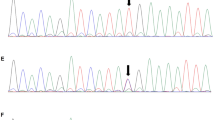

Chromosome analysis in peripheral lymphocytes showed a normal male karyotype (46,XY) at a banding resolution of 400 bands per haploid genome. Whole exome sequencing analysis was performed on the patient, a large heterozygous copy number deletion on CREBBP gene, from exon 29 to exon 31 (chr16 3778026-3781885) was identified on the patient, this mutation was de novo and not found on his parents by sanger sequencing (Fig. 3). We used long PCR and Sanger sequencing to determine the location of the breakpoint on the patient, and found that the upstream breakpoint position of the heterozygous copy number deletion is chr16:3745392, and the downstream breakpoint position is chr16:3783895. It is confirmed that the size of the heterozygous copy number deletion is 38503 bp, and a sequence of nearly 300 bp has been inserted at the breakpoint. It might be caused when DNA double-strand break damage is repaired (Fig. 3). This heterozygous copy number deletion region chr16:3745393-3783894 covers the exon 1 region and part of the intron 1 region of the TRAP1 gene, and the entire region from intron 27 to exon 30 of the CREBBP gene. In general, this pathogenic heterozygous deletion is the causative mutation for the disease phenotype in this family.

Pedigree of affected family (A). Whole exome sequencing analysis identified a large heterozygous copy number deletion on CREBBP gene, from exon 29 to exon 31 (chr16 3778026-3781885) on the patient, this mutation was de novo and not found on his parents by sanger sequencing (B). Long PCR and Sanger sequencing showed that the heterozygous copy number deletion region chr16:3745393-3783894 covers the exon 1 region and part of the intron 1 region of the TRAP1 gene, and the entire region from intron 27 to exon 30 of the CREBBP gene (C, D)

Although whole exome sequencing has the advantage of high efficiency and convenience in screening pathogenic genes, the importance of traditional sanger sequencing cannot be ignored. For example, in our research, we find a large deletion mutation of exon 29 to 31 on CREBBP gene, after verification by Sanger sequencing, it was finally confirmed to be the mutation covers the exon 1 region and part of the intron 1 region of the TRAP1 gene, and the entire region from intron 27 to exon 30 of the CREBBP gene.